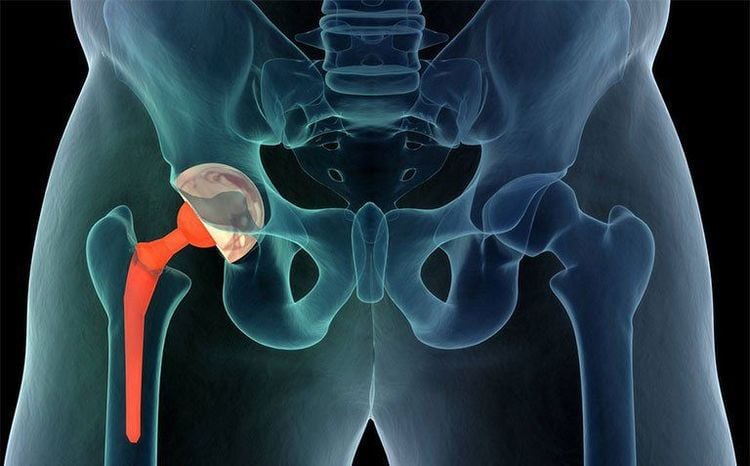

Thay khớp háng nhân tạo là biện pháp điều trị hiệu quả nhất và được xem là lựa chọn cuối cùng trong các trường hợp thoái hóa khớp háng nặng. Phương pháp này thường được chỉ định khi bệnh nhân đã áp dụng mọi phương pháp điều trị khác nhưng không mang lại hiệu quả giảm đau hoặc khi khớp háng bị tổn thương nghiêm trọng, không còn khả năng phục hồi.

Trong quá trình thay khớp, phần chỏm xương đùi và ổ cối của xương chậu bị tổn hại sẽ được thay thế bằng các bộ phận khớp nhân tạo. Đặc biệt, phẫu thuật thay khớp háng là giải pháp hàng đầu cho những bệnh nhân bị dính bề mặt khớp hoàn toàn, không thể vận động chân hoặc đi lại bình thường.

Với sự tiến bộ của y học hiện đại, kỹ thuật thay khớp háng ngày càng hoàn thiện, mang lại nhiều lợi ích vượt trội. Các bác sĩ hiện nay có trình độ chuyên môn cao, cùng với việc sử dụng các vật liệu thay khớp tiên tiến, giúp phẫu thuật trở nên an toàn và hiệu quả hơn. Một số ưu điểm nổi bật bao gồm: vết mổ nhỏ, hạn chế tổn thương đến các mô mềm xung quanh khớp, thời gian mổ được rút ngắn và đảm bảo chính xác phần khớp cần thay thế.

Ngoài ra, kỹ thuật thay khớp háng hiện đại còn giúp giảm thiểu nguy cơ nhiễm trùng và rút ngắn thời gian nằm viện. Chỉ sau khoảng 5 đến 7 ngày, bệnh nhân có thể xuất viện và bắt đầu tập luyện phục hồi chức năng. Đặc biệt, những năm gần đây, công nghệ in 3D trong phẫu thuật thay toàn bộ khớp háng đã mở ra một hướng đi mới, mang lại cơ hội cải thiện chất lượng cuộc sống cho bệnh nhân thoái hóa khớp háng.

Phẫu thuật thay khớp háng nhân tạo sử dụng công nghệ 3D hiện đại mang lại tỷ lệ thành công cao hơn so với phương pháp phẫu thuật truyền thống. Điểm đặc biệt của công nghệ này là mỗi bệnh nhân được thiết kế một kế hoạch phẫu thuật riêng biệt, lựa chọn loại khớp nhân tạo phù hợp nhằm tối ưu hóa hiệu quả điều trị.

Phương pháp này không chỉ giảm đáng kể nguy cơ biến chứng như trật khớp, lỏng khớp hoặc gãy xương mà còn rút ngắn thời gian hồi phục. Chỉ sau 2-4 tuần kết hợp với vật lý trị liệu, bệnh nhân có thể trở lại sinh hoạt bình thường. Phẫu thuật thay khớp háng đã mở ra cơ hội giúp người bệnh chấm dứt các cơn đau xương khớp dai dẳng, cải thiện khả năng vận động và nâng cao chất lượng đời sống hằng ngày của người bệnh.